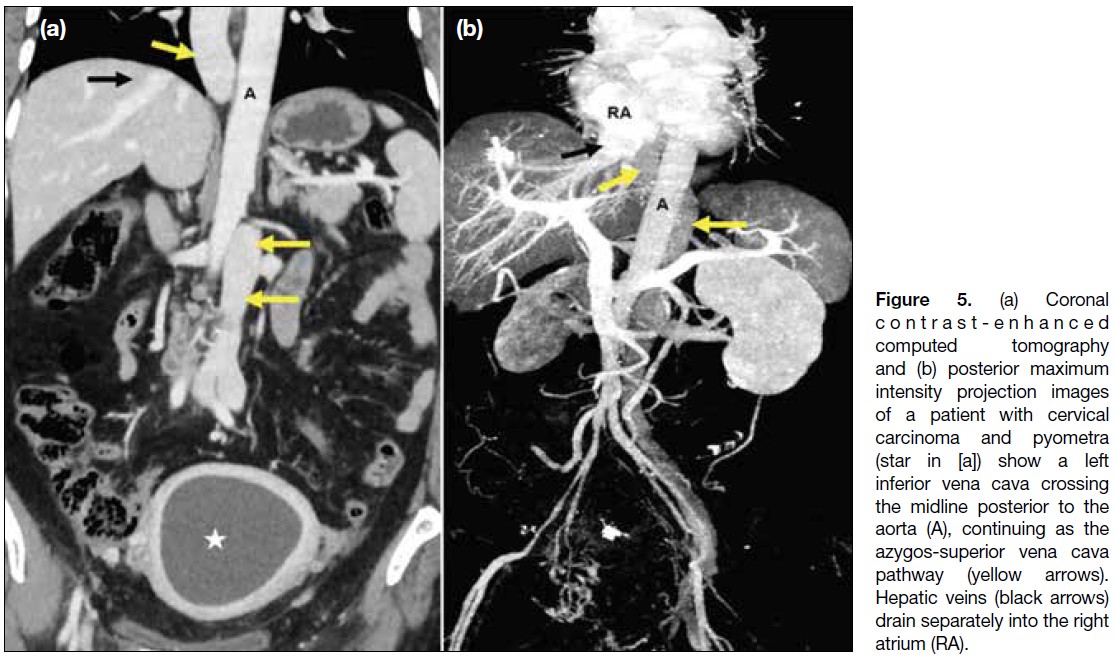

Figure 5. (a) Coronal

contrast-enhanced computed tomography

and (b) posterior maximum

intensity projection images

of a patient with cervical

carcinoma and pyometra

(star in [a]) show a left

inferior vena cava crossing

the midline posterior to the

aorta (A), continuing as the

azygos-superior vena cava

pathway (yellow arrows).

Hepatic veins (black arrows)

drain separately into the right

atrium (RA).